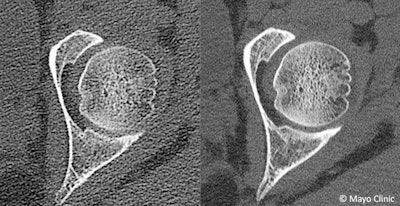

- Musculoskeletal -- Bone mineral density may be measured on almost every dual-energy scan, which is not possible with conventional CT imaging, Noël pointed out.